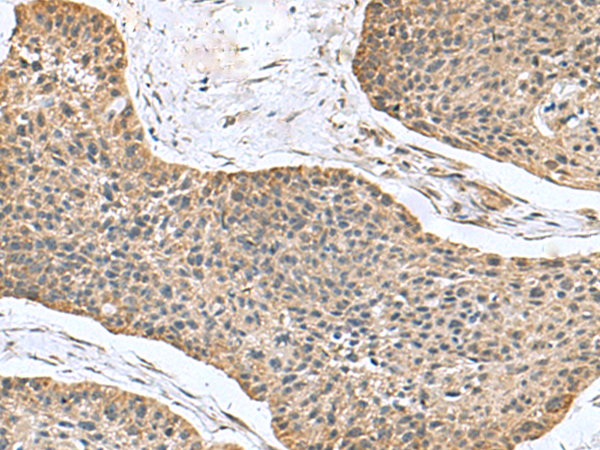

分类: 科研抗体货号: P03426别名: EBP1; HG4-1; p38-2G4应用: WB,IHC反应种属: Human, Mouse, Rat